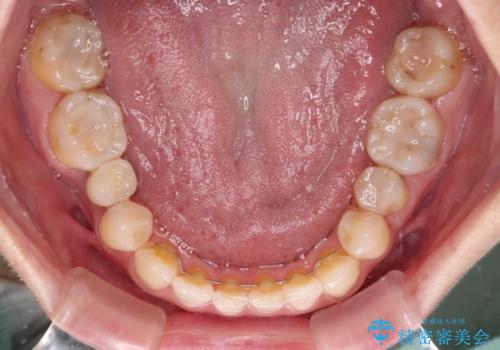

前歯のクロスバイトと治療が必要なむし歯 矯正とセラミックの総合歯科治療

前歯のクロスバイトはインビザラインで改善し、抜歯が必要な部分はインプラントを、その他むし歯が進行している歯はセラミッククラウンによる補綴治療することとしました。

仕事がお忙しく、インビザラインをあまりしっかりと使用できなかったようで、何とか長い期間をかけて歯列を整えることができました。

磨きにくく、何度もむし歯治療を繰り返していた前歯をスッキリと整えることができました。